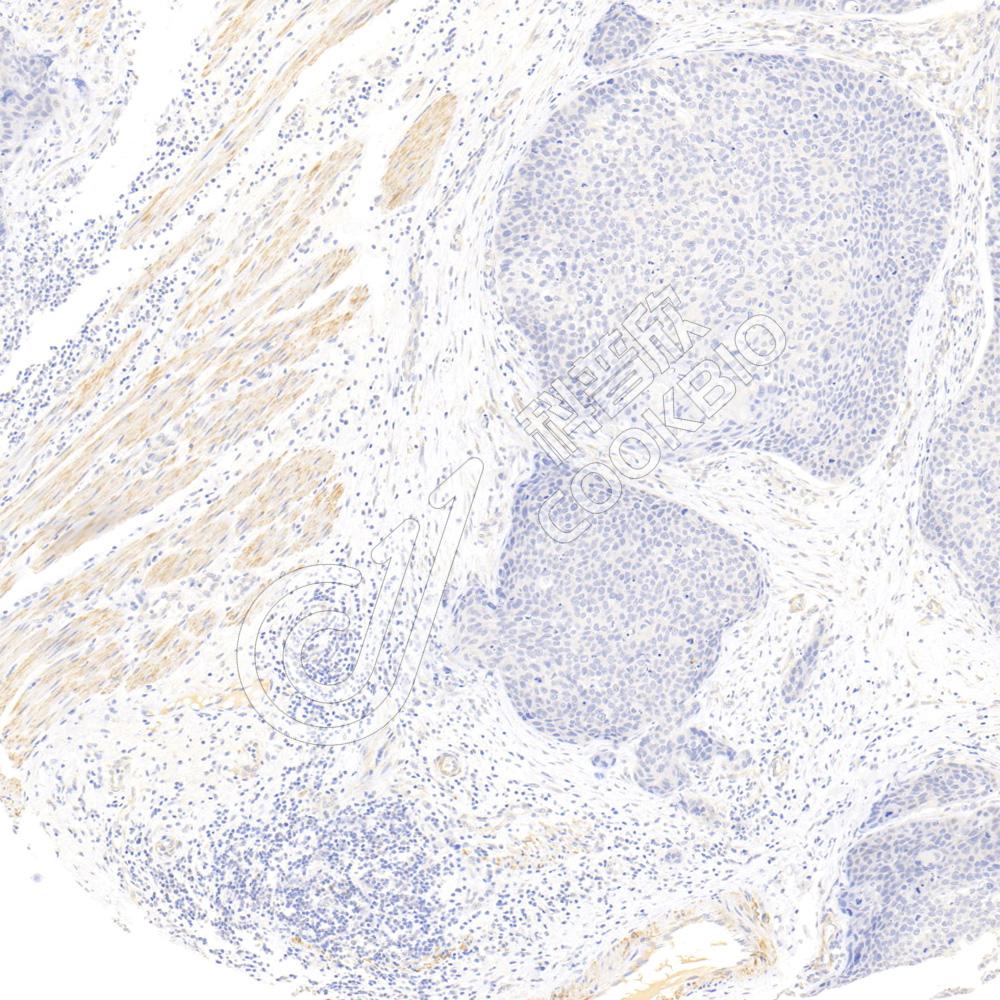

IHC检测PRPH2/RDS蛋白(货号 K1340761).

样品: 小鼠眼球, 4%多聚甲醛 (货号KSG1101) 固定12-24小时.

抗原修复: 柠檬酸抗原修复液(干粉, pH 6.0) (KSG1201), 98℃, 20分钟.

—抗: 1: 3000稀释, 4℃ 孵育过夜.

二抗: S-vision免疫组化多聚二抗(山羊抗兔),即用型 (货号KB3906), 室温孵育20分钟.